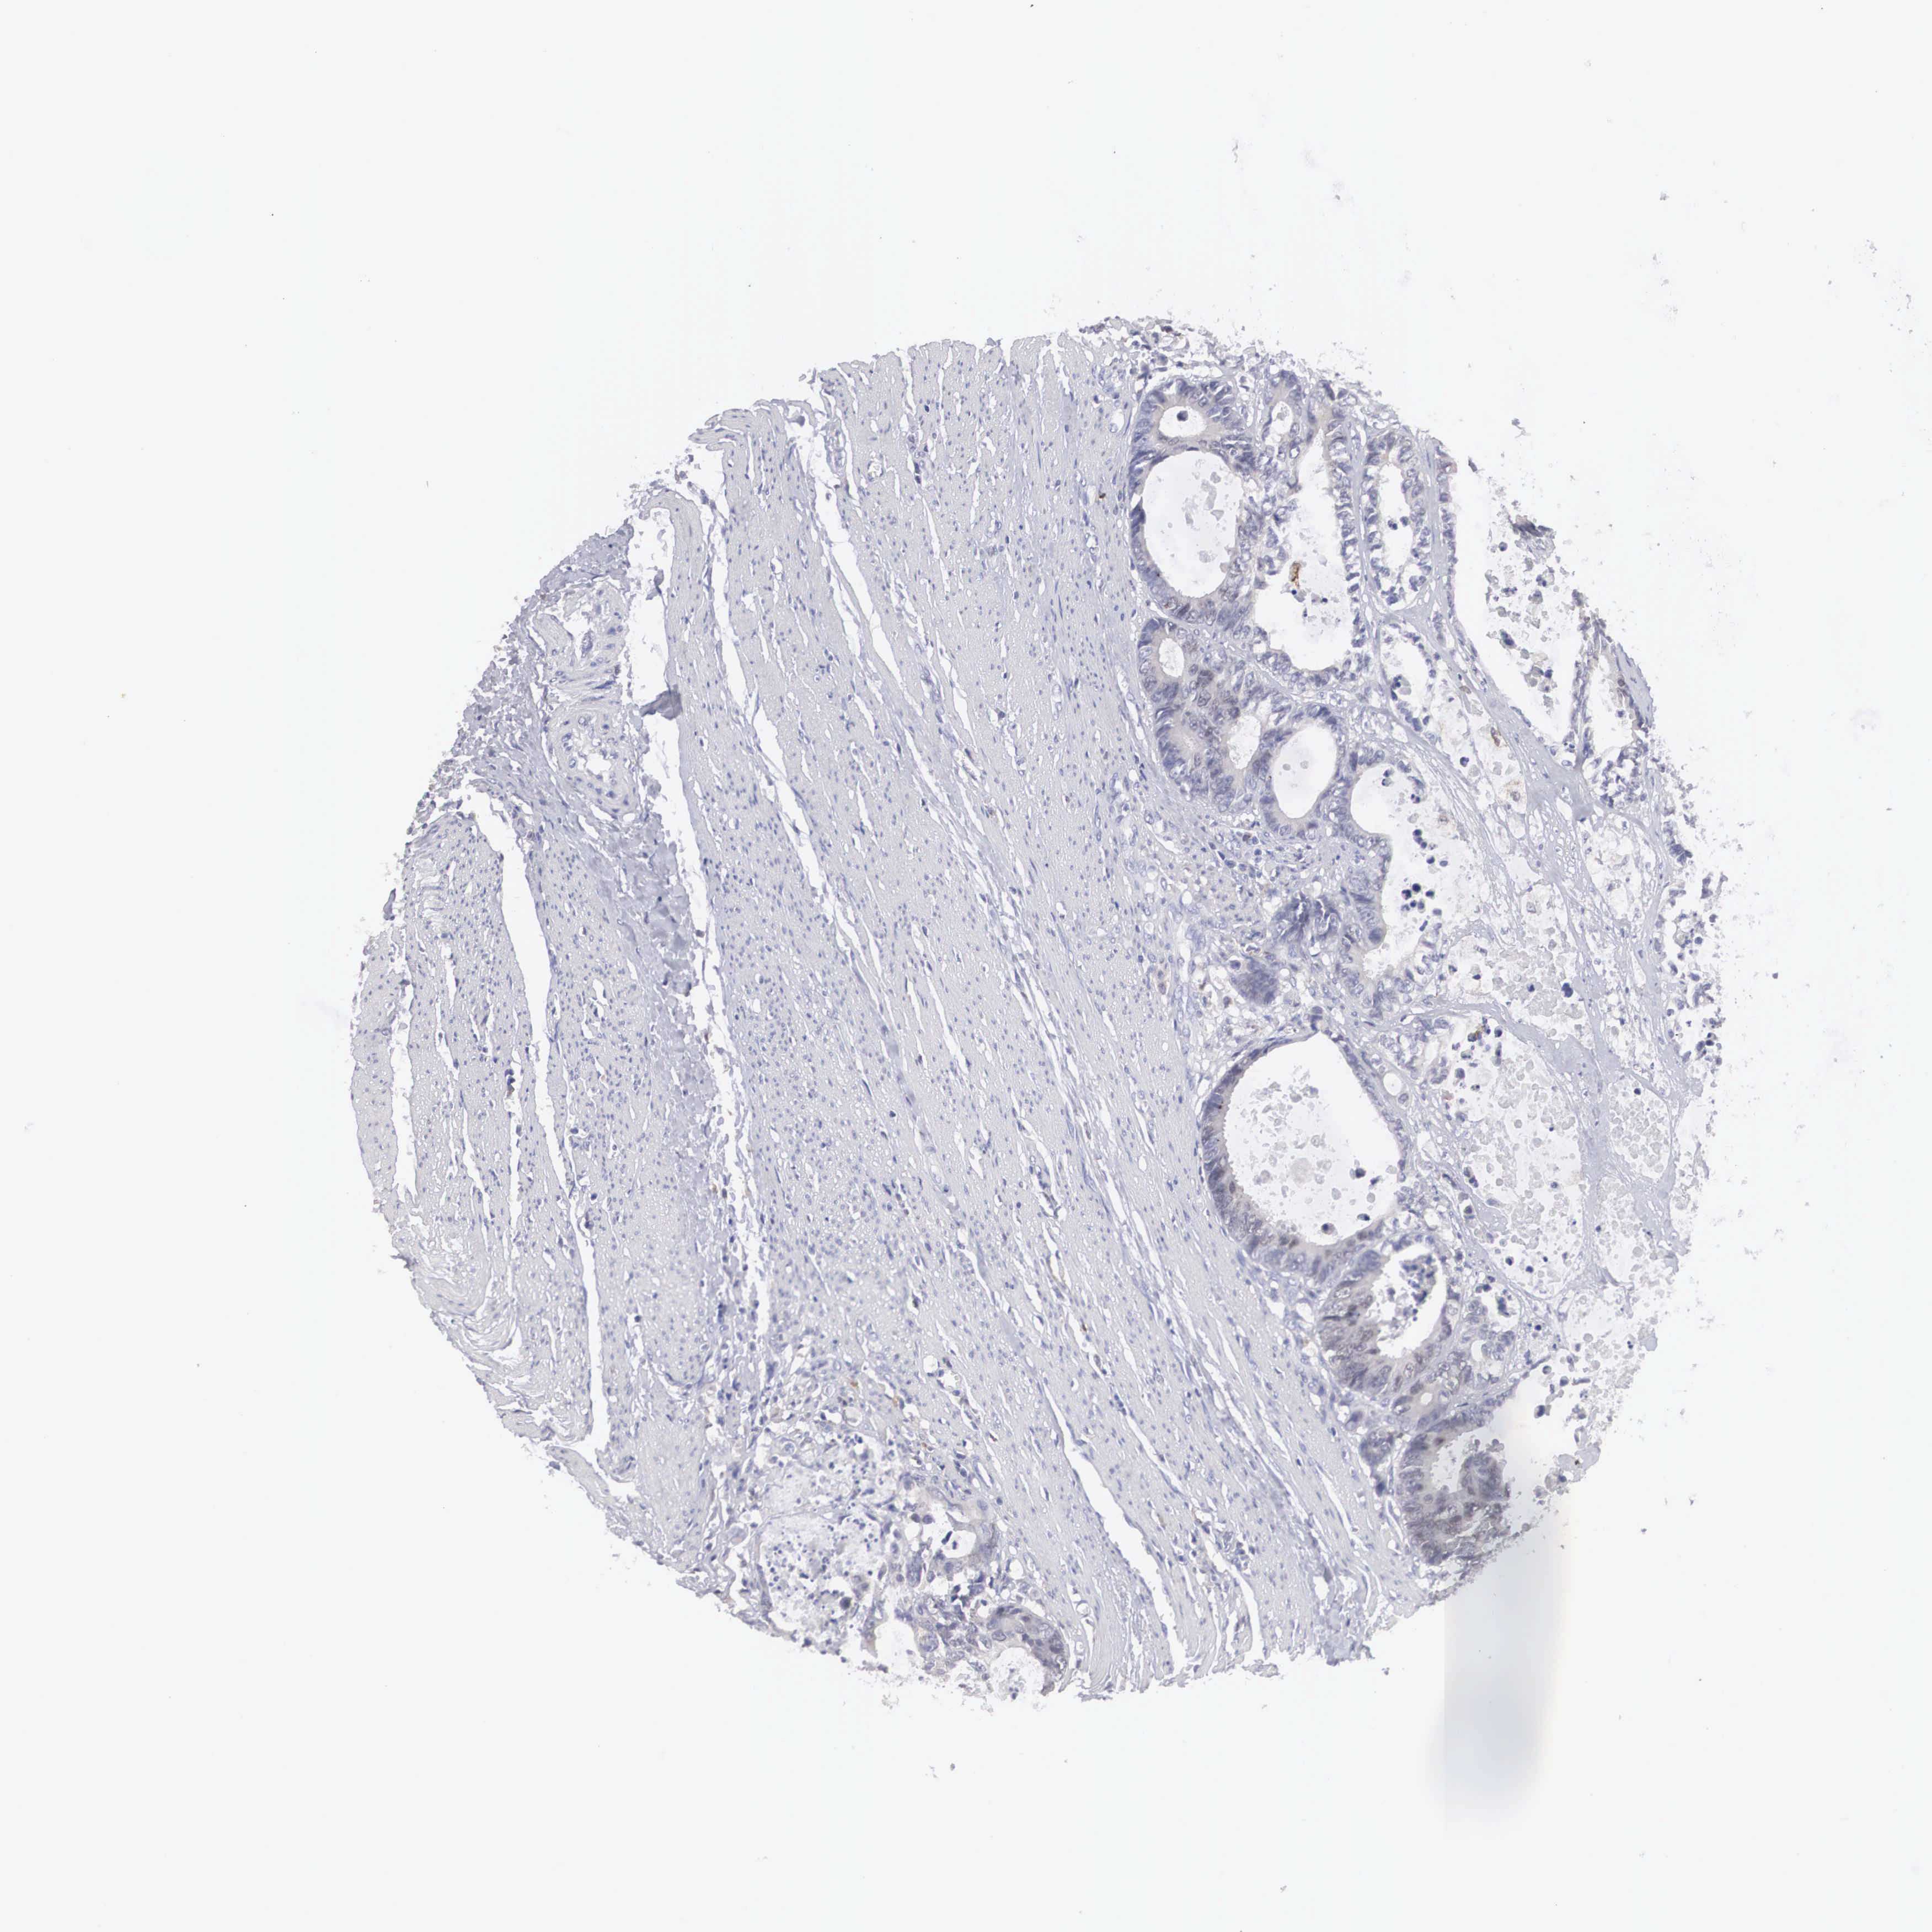

CANCER COLORECTAL CANCER Show tissue menu

Colorectal cancer

Human cancer

Colon adenocarcinoma